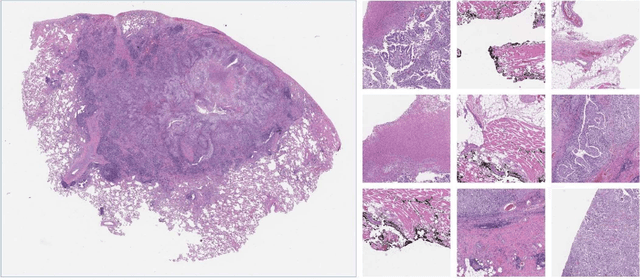

Abstract:Despite the great potential of machine learning, the lack of generalizability has hindered the widespread adoption of these technologies in routine clinical practice. We investigate three methodological pitfalls: (1) violation of independence assumption, (2) model evaluation with an inappropriate performance indicator, and (3) batch effect and how these pitfalls could affect the generalizability of machine learning models. We implement random forest and deep convolutional neural network models using several medical imaging datasets, including head and neck CT, lung CT, chest X-Ray, and histopathological images, to quantify and illustrate the effect of these pitfalls. We develop these models with and without the pitfall and compare the performance of the resulting models in terms of accuracy, precision, recall, and F1 score. Our results showed that violation of the independence assumption could substantially affect model generalizability. More specifically, (I) applying oversampling before splitting data into train, validation and test sets; (II) performing data augmentation before splitting data; (III) distributing data points for a subject across training, validation, and test sets; and (IV) applying feature selection before splitting data led to superficial boosts in model performance. We also observed that inappropriate performance indicators could lead to erroneous conclusions. Also, batch effect could lead to developing models that lack generalizability. The aforementioned methodological pitfalls lead to machine learning models with over-optimistic performance. These errors, if made, cannot be captured using internal model evaluation, and the inaccurate predictions made by the model may lead to wrong conclusions and interpretations. Therefore, avoiding these pitfalls is a necessary condition for developing generalizable models.